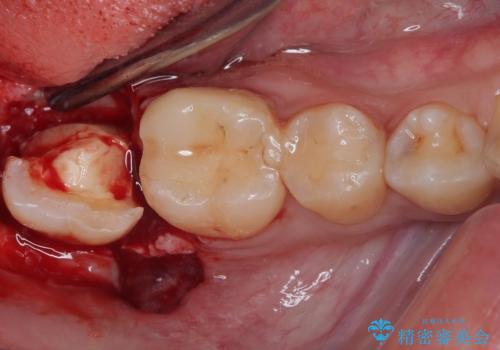

- 右下の奥歯が大きく欠けてしまったのを治したいと来院された患者様です。

舌側の歯冠がなくなってしまっていて、健全な歯質が歯茎の下にある状態です。

このままの状態だと土台がたてられず被せものがいれられないため、歯肉の切除と歯槽骨の形態修正を行い、歯の健全な部分が歯肉の外に出てくるようにしたうえで、オールセラミッククラウンによる補綴治療を行うこととしました。